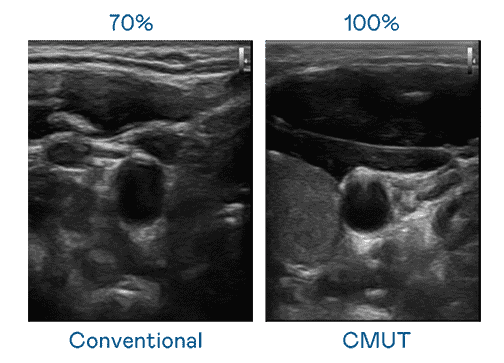

CMUT 技术是一种用电容式微机电元件来产生超音波讯号的技术。。。与传统 PZT 压电式技术相比,,,CMUT 频宽增加 30%,,,,更宽频的超音波讯号让影像解析度大幅提升,,,是实现高影像品质医疗超音波扫描、、、促进精准医疗发展的关键技术。。。。

大频宽带来超清晰影像

超音波影像的解析度高低,,首先取决于探头能发出的讯号频宽。。。z6尊龙 CMUT 可提供高清晰的超音波讯号,,提供高频宽、、、高灵敏度、、、、影像纹理细节更高的超音波影像,,,协助医护人员缩短影像判读时间及利用精准的医疗影像进行诊断。。。。